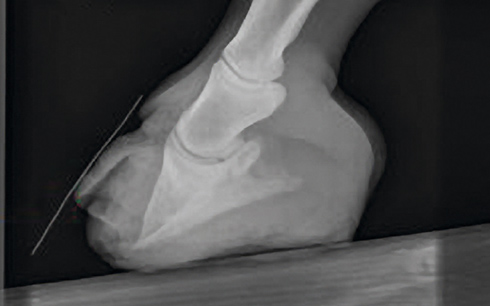

Pedal bone fractures – a broken bone that doesn’t have to signal the end